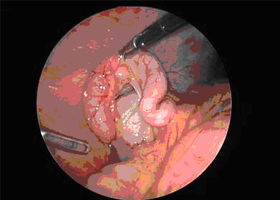

Αντιμετώπιση: Η αντιμετώπιση της Οξείας Σκωληκοειδίτιδας είναι αποκλειστικά χειρουργική. Η σκωληκοειδεκτομή πρέπει να γίνεται άμεσα προτού η φλεγμονή εξελιχθεί σε περιτονίτιδα, η οποία αυξάνει την βαρύτητα του χειρουργείου καθώς και τις επιπλοκές του. Η σκωληκοειδεκτομή μπορεί να γίνει και με ανοικτή και με λαπαροσκοπική μέθοδο. Κλασικά η σκωληκοειδεκτομή εκτελείται από μία μικρή τομή στο δεξιό κάτω μέρος της κοιλιάς. Στην εποχή, μας πολύ συχνά πραγματοποιείται η λαπαροσκοπική σκωληκοειδεκτομή δια μέσου τριών μικρών τομών στην κάτω κοιλιά και με την βοήθεια ειδικών λαπαροσκοπικών εργαλείων. Με την λαπαροσκοπική προσπέλαση, όταν βέβαια αυτή είναι εφικτή, έχουμε λιγότερο μετεγχειρητικό πόνο, γρηγορότερη ανάρρωση και πιο καλό έλεγχο της κοιλιάς σε σχέση με την ανοικτή σκωληκοειδεκτομή.